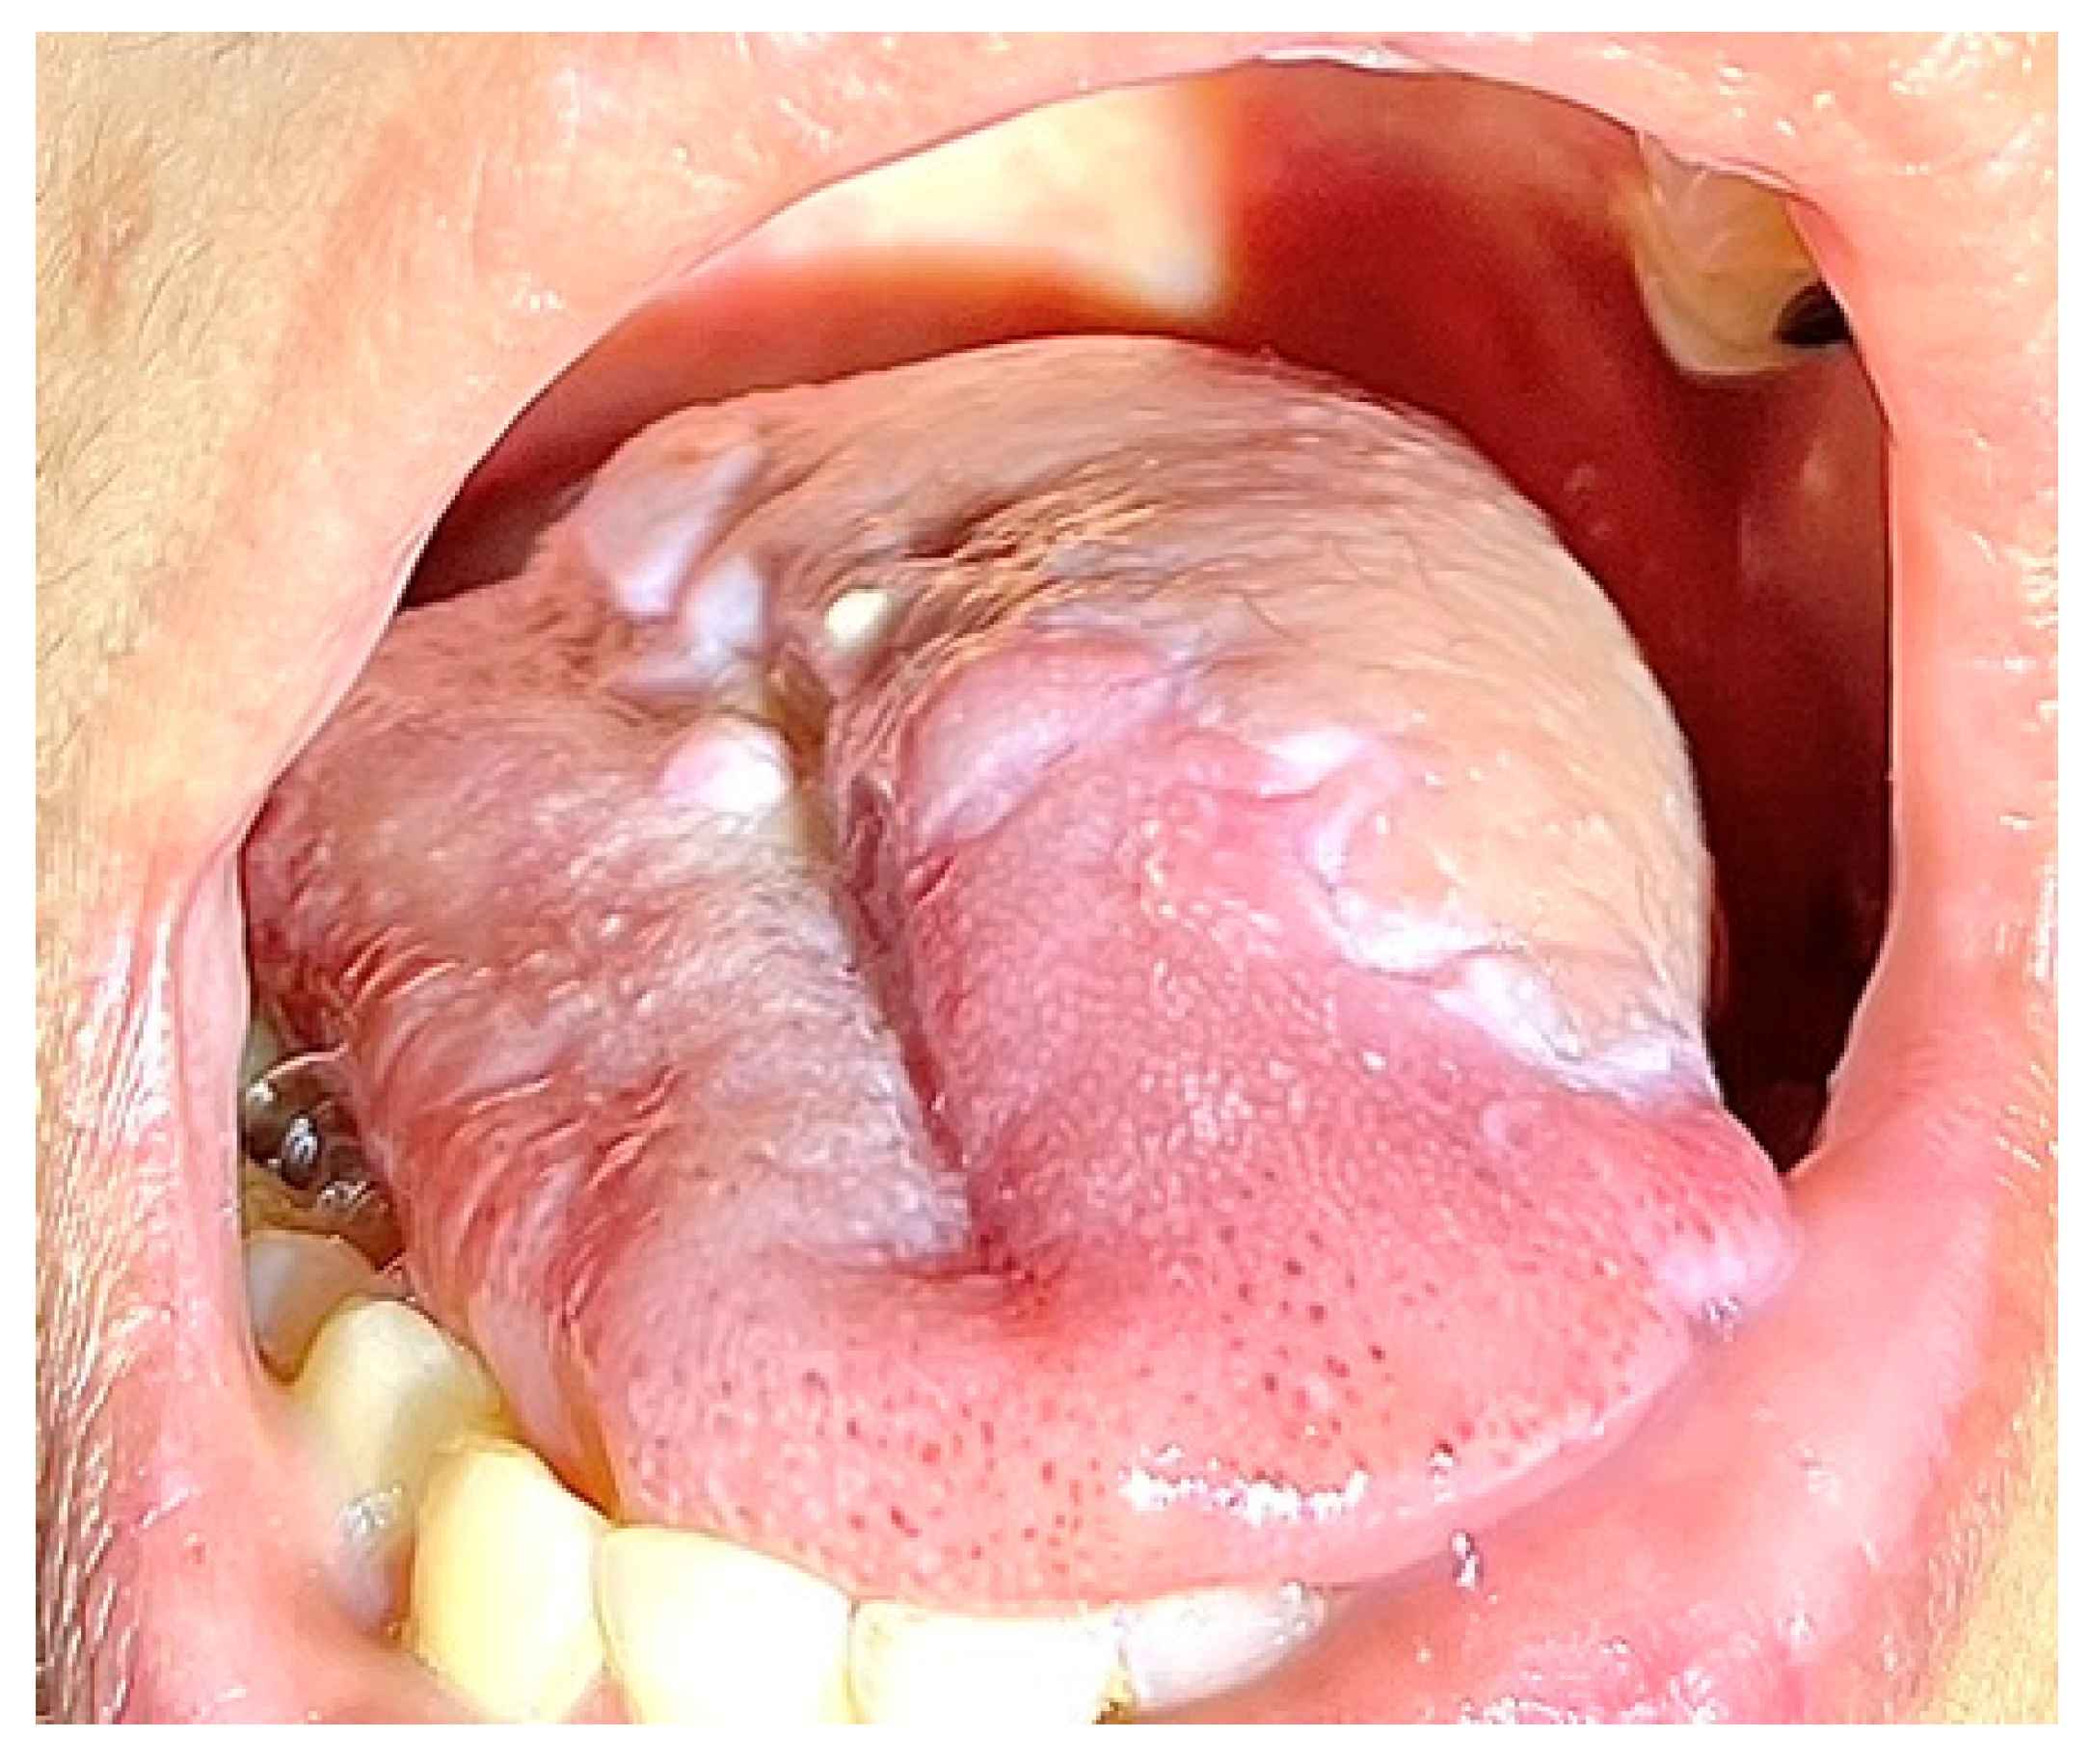

3.4. Case 4

A 58-year-old male with pT2N0M0 buccal/commissural squamous cell carcinoma underwent composite resection and radial forearm free flap reconstruction in August 2024. Cervical microvascular anastomoses were completed using the Olympus Orbeye 4K 3D exoscope camera system (Olympus Deutschland GmbH, Hamburg, Germany). Implantable Cook microdoppler dual-channel monitoring system was utilized perioperatively to ensure microvascular patency and flow (Figure 11, Figure 12, Figure 13 and Figure 14).

Figure 11. Case 4—Ablative defect.